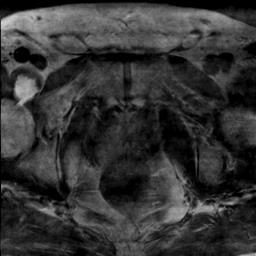

Modern deep neural networks struggle to transfer knowledge and generalize across diverse domains when deployed to real-world applications. Currently, domain generalization (DG) is introduced to learn a universal representation from multiple domains to improve the network generalization ability on unseen domains. However, previous DG methods only focus on the data-level consistency scheme without considering the synergistic regularization among different consistency schemes. In this paper, we present a novel Hierarchical Consistency framework for Domain Generalization (HCDG) by integrating Extrinsic Consistency and Intrinsic Consistency synergistically. Particularly, for the Extrinsic Consistency, we leverage the knowledge across multiple source domains to enforce data-level consistency. To better enhance such consistency, we design a novel Amplitude Gaussian-mixing strategy into Fourier-based data augmentation called DomainUp. For the Intrinsic Consistency, we perform task-level consistency for the same instance under the dual-task scenario. We evaluate the proposed HCDG framework on two medical image segmentation tasks, i.e., optic cup/disc segmentation on fundus images and prostate MRI segmentation. Extensive experimental results manifest the effectiveness and versatility of our HCDG framework.